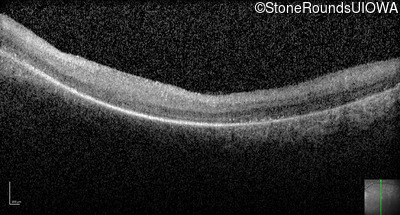

Optical Coherence Tomography - Left -

No Light Perception

Exemplar

Expanded OCT Stack

×